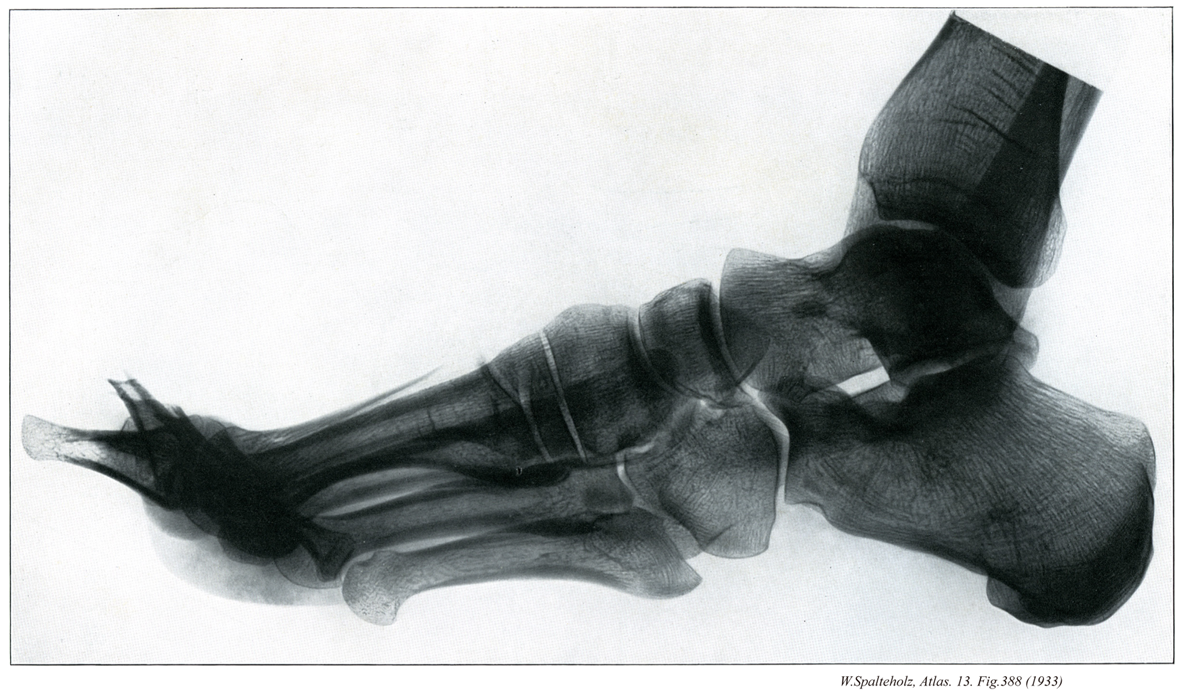

【Foot

足

Pes】

→(足根部、中足部および趾(足の指)にわけられる。足根部は足根骨(7個)、中足部は中足骨(5本)、趾は趾骨(14個)が基礎となっている。皮膚節において第四腰神経、第五腰神経、第一仙骨神経のレベル)